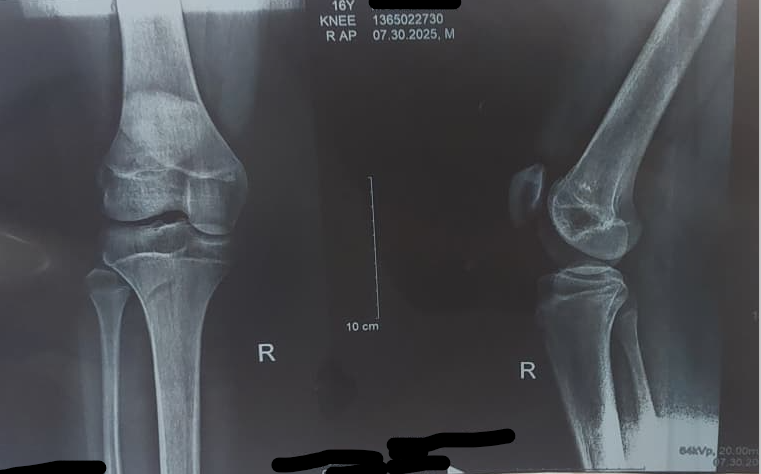

and this is the scan if anybody is interested

Bones stop growing from out to in meaning the distal tibial growth plate closes, then the proximal tibial growth plate then the distal femur and so on so fourth. so is your tibia and distal femur closed or is it just the tibia? if both are closed then you could have grown from the proximal femur. that's one of the last to grow alongside your spine.